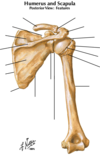

Humerus and Scapula

Deltoid

Origin : lateral third of the clavicle, the acromion, and the spine of scapula

Insertion : deltoid tuberosity of the humerus

Innervtion : axillary nerve

Because of its origin, the functions vary depending upon the part that is functioning. From a clinical viewpoint, its function as an abductor of the upper extremity is most significant.

Axillary nerve to deltoid enters posterior deep surface

The subacromial bursa (subdeltoid bursa) is located deep to the deltoid and acromion

Calcification of the supraspinatus tendon leads to inflammation of the bursa, causing pain on abduction of the upper extremity (painful arc syndrome).

Supraspinatus and Infraspinatus

Origin : respective fossae of the scapula

Insertion : greater tubercle of the humerus.

Innervation : suprascapular nerve

Blood supply : suprascapular artery, a branch of the thyrocervical trunk that originates from the subclavian artery

Teres minor

Origin : lateral border of the scapula

Insertion : greater tubercle of the humerus

Innervation : axillary nerve

Action : along with the infraspinatus, it laterally rotates the upper extremity

Teres major

Origin - inferior angle of the scapula

Insertion : medial lip of the intertubercular groove of the humerus

Innervation : lower subscapular nerve